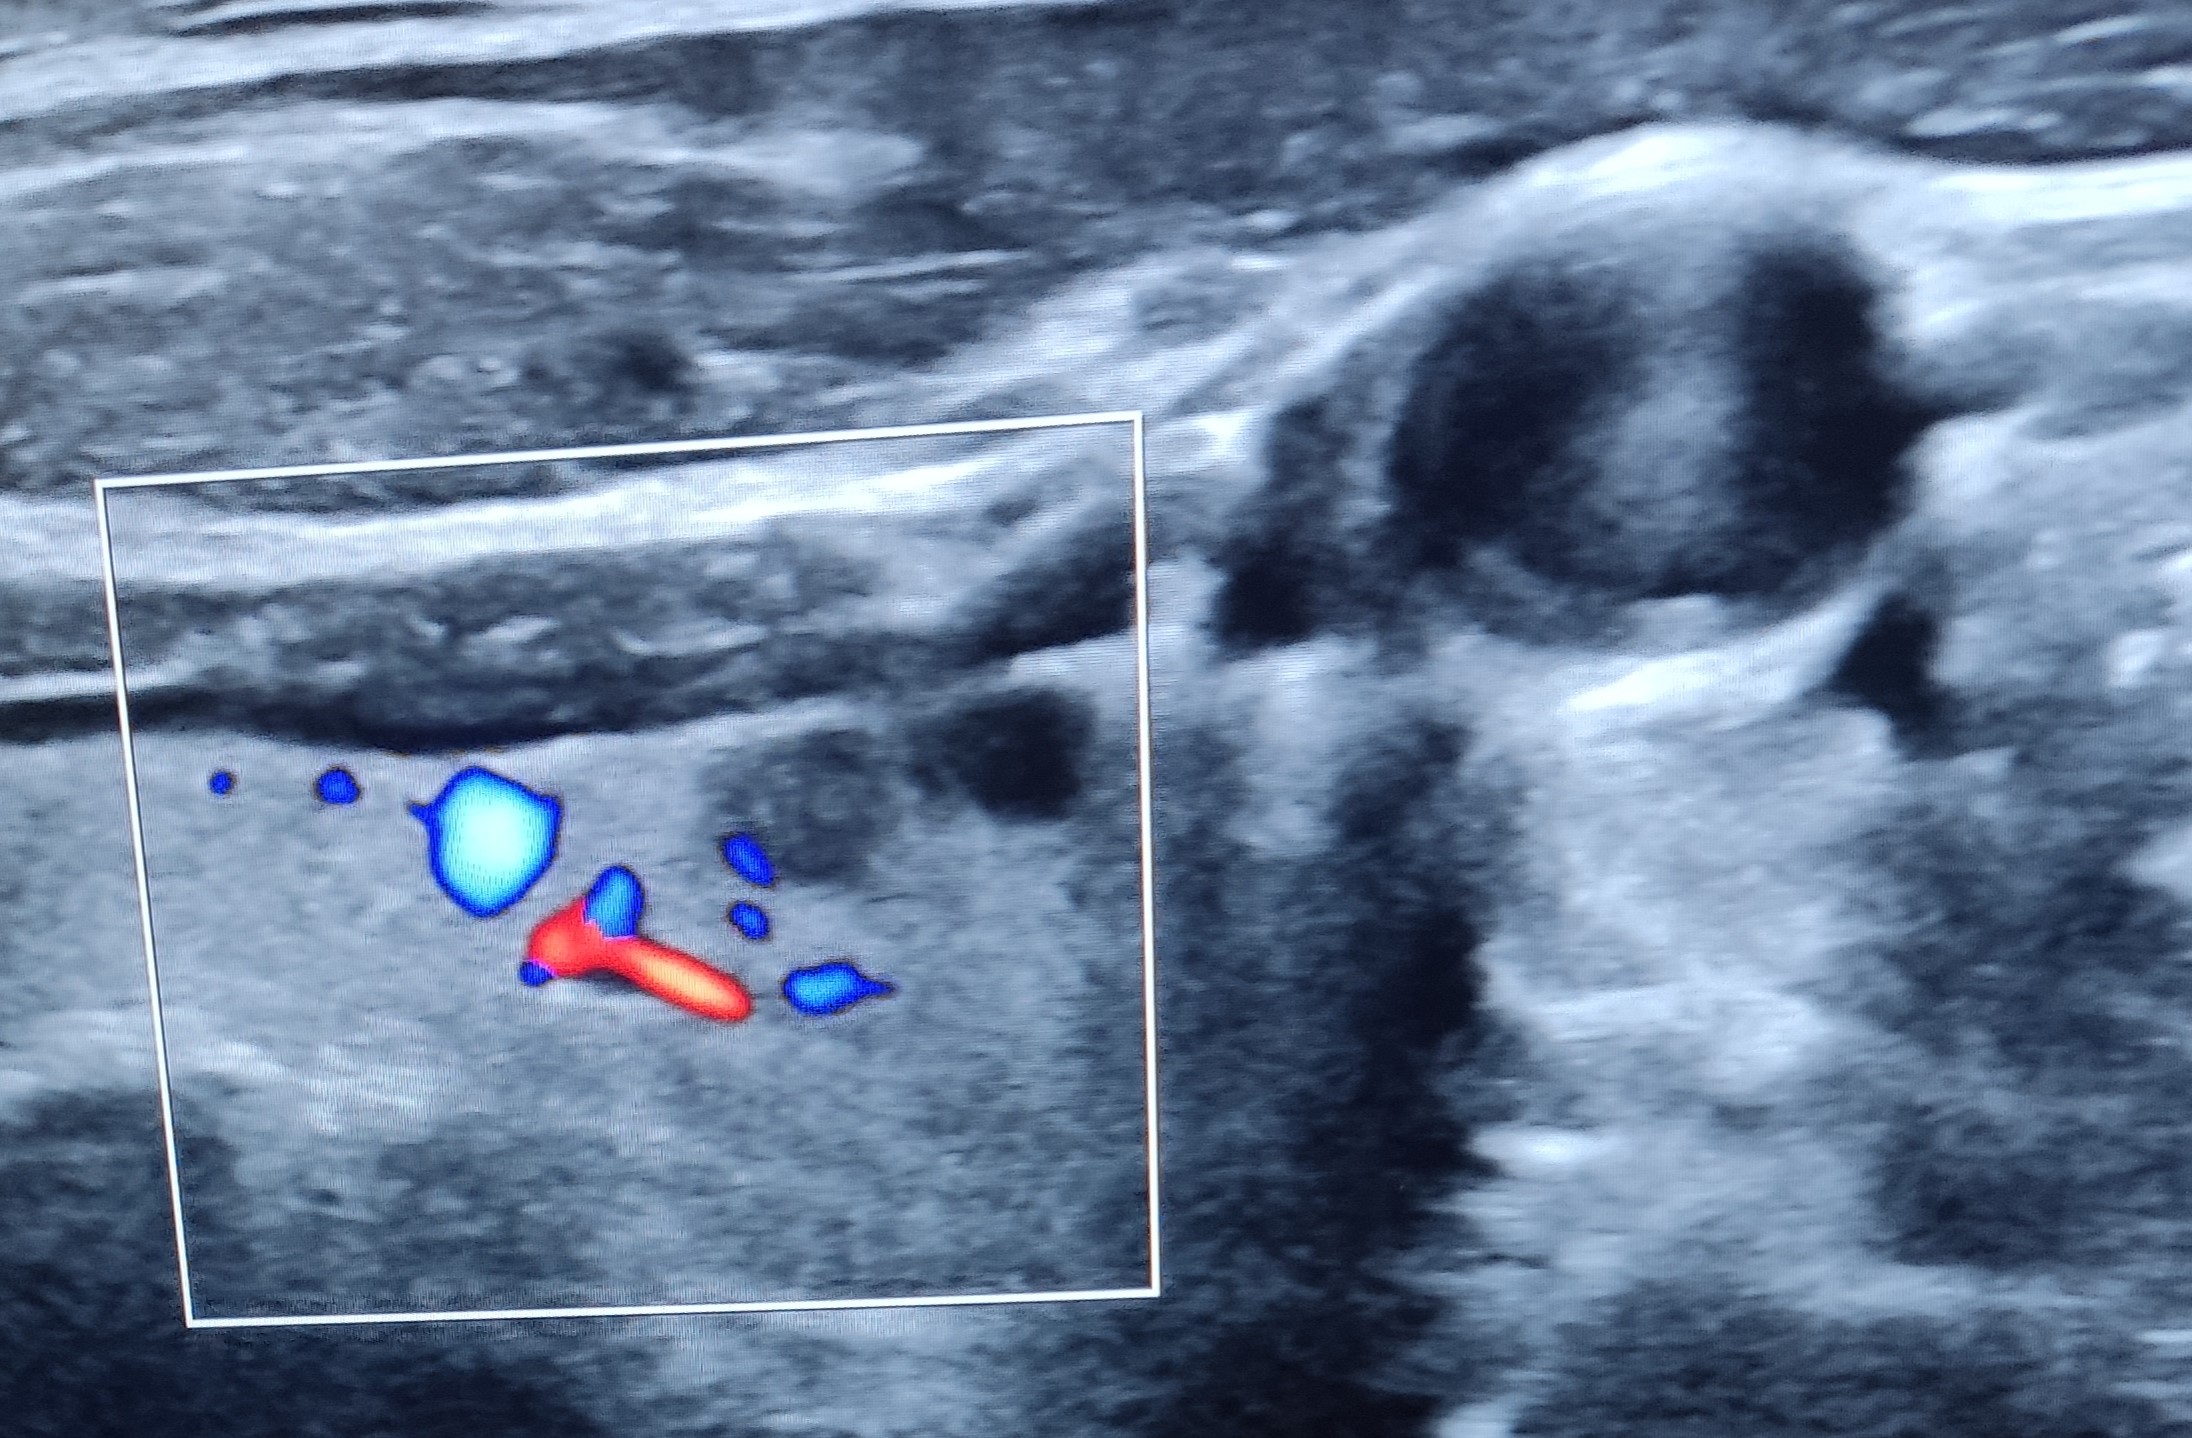

En la ecografía realizada en consulta se realizan diferentes mediciones, descartando hipertrofia glandular o bocio. Explorando ambos lóbulos posteriormente, se objetivan dos imágenes quísticas, subcentimétricas, anecoicas, con bordes bien definidos y refuerzo posterior, todo ello compatible con quiste benigno, de contenido posiblemente líquido o coloide, sin captación de Doppler.

En  el lóbulo izquierdo se objetiva una lesión algo mas hiperecogenica, tambien subcentimetrica, sin captacion de dopler color ni refuerzo posterior, que impresiona de contenido algo sólido, con bordes bien definidos y regulares.